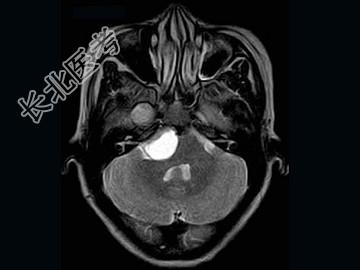

- 单项选择题女,41岁, 头痛,头晕, 走路不稳1个月余,MRI检查, 最可能的诊断为 ( )

A、听神经瘤

B、脑膜瘤

C、三叉神经瘤

D、胆脂瘤

E、神经纤维瘤